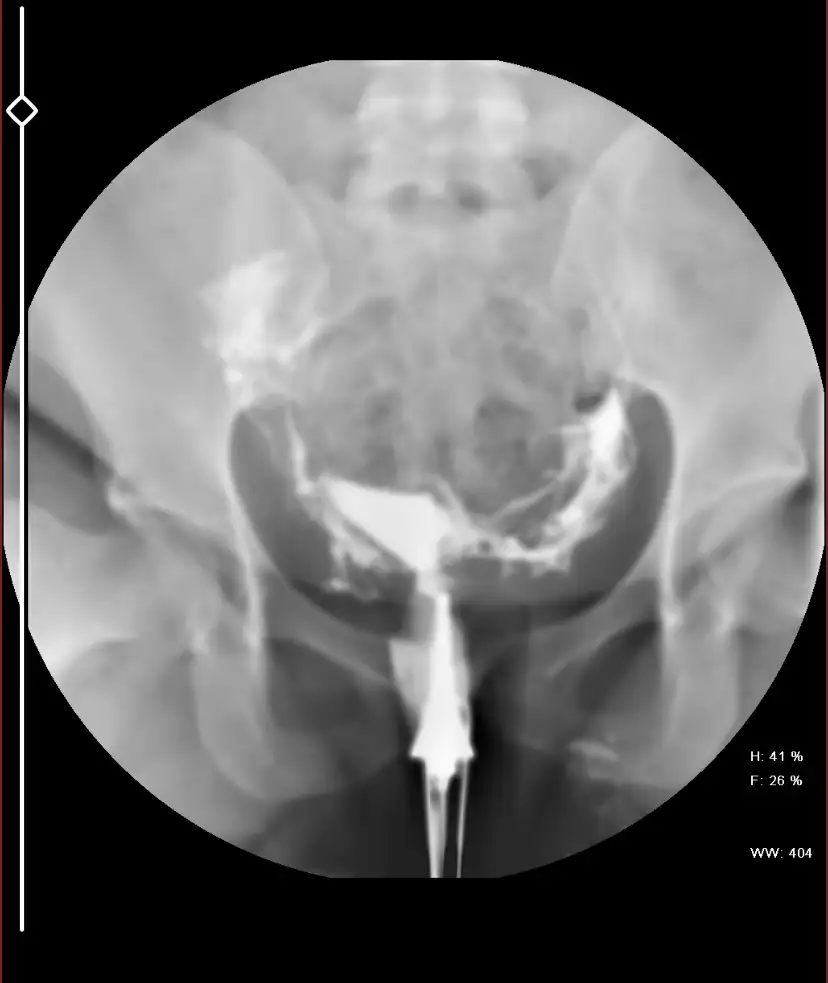

Zaten çeken kişiye sorunca söylüyor benim gördüğüm tek tüp tamamen açık,diğerinde varsa da tıkanıklık işlemden sonra açılmıştırHaklisin bende biliyorum. Ama korkudan zamanda gecmiyor belki anlayan olur diye sordum saol yinede

Soylemedi gicik biriydi ucgun sonra gel dedi oda bidaha carsambaya kaldi her gel dedi an gidemiyoruzZaten çeken kişiye sorunca söylüyor benim gördüğüm tek tüp tamamen açık,diğerinde varsa da tıkanıklık işlemden sonra açılmıştır

İnsallah oyledir cok saolGörüntülerde sıvı iki tüptende karın boşluğuna yayılmış gibi gördüm ben ama yine de rapor da belli olur

Gayet açık tüplerin o beyazlıklar varta yukarı doğru olan onlar sıvının geçtiğini gösteriyor,bi kaç ay içinde hayırlı haber alırsınSoylemedi gicik biriydi ucgun sonra gel dedi oda bidaha carsambaya kaldi her gel dedi an gidemiyoruz

Esime nasil kiziyorum butun cileyi biz cekelim sefasini siz surunÖf ya nedir bu kadınların çektiği çileşansına öylesi denk gelmiş çok şükür atlatmışsın bu arada resimlere baktım da benim görüşüm bence tüp kapalıydıysa açılmıştır ben açılmış diye görüyorum